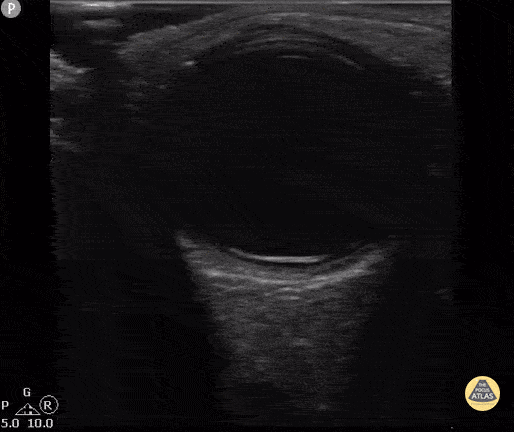

8 year old with blurry vision, acuity 20/70 and retinal detachment confirmed by dilated eye exam. Contributor: Antonio Riera, MD